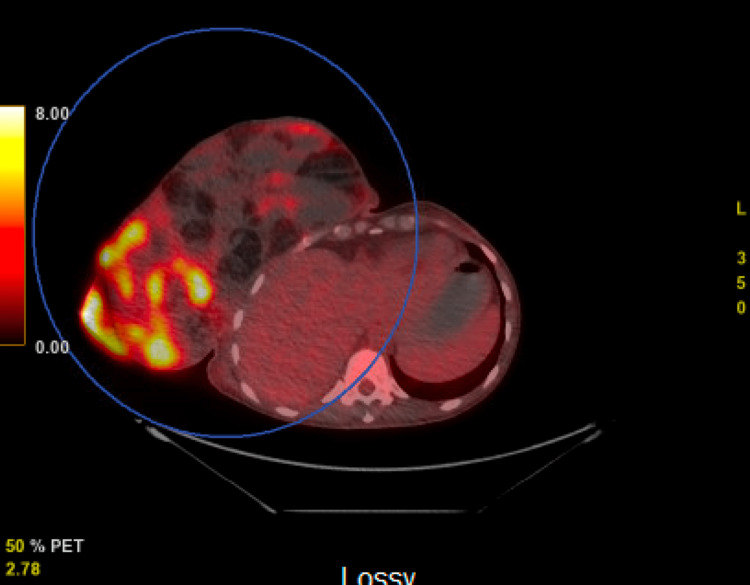

A positron emission tomography (PET) scan was then obtained revealing a large heterogeneous soft tissue and fatty mass extending from the right breast demonstrating areas of hypermetabolic activity with a centrally cystic or necrotic mediastinal lesion noted (Figures 4, 5). There was no evidence of metastatic disease within the abdomen and pelvis.

Figure 4. Positron emission tomography (PET) scan revealing a large heterogeneous soft tissue and fatty mass extending from the right breast demonstrating areas of hypermetabolic activity.

Figure 5. Positron emission tomography (PET) scan revealing a large heterogeneous soft tissue and fatty mass extending from the right breast demonstrating areas of hypermetabolic activity with a centrally cystic or necrotic mediastinal lesion noted. There was no evidence of metastatic disease within the abdomen and pelvis.